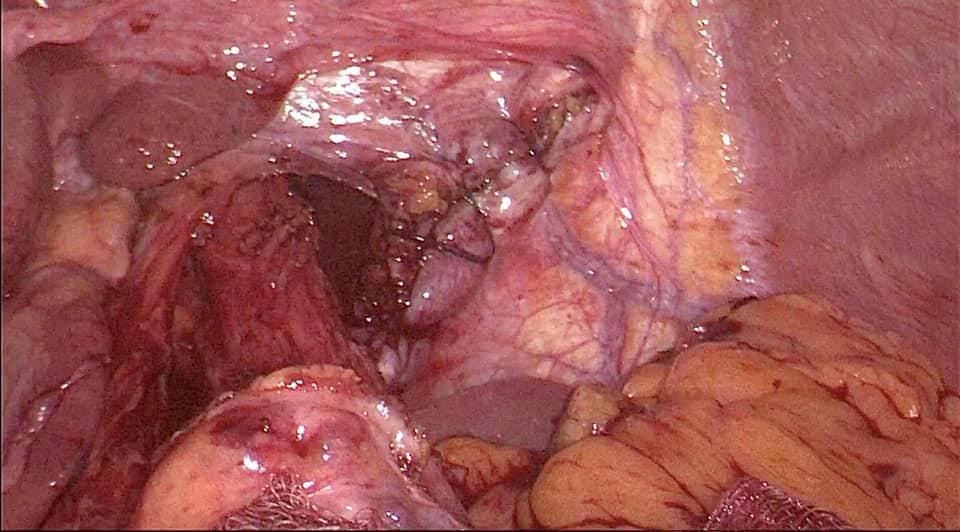

Laparoscopic total proctocolectomy and ileal pouch surgery for ulcerative colitis

Mr SR aged 40 was suffering from steroid resistant ulcerative colitis with severe bloody diahhorea 10-15 times a day with anemia and progressive weight loss not responding to medications. He underwent laparoscopic total proctocolectomy and ileal pouch surgery 2 years ago, performed by Dr. Phani Krishna Ravula. 2 years later on follow up He is now of all medication and cured of ulcerative colitis and back to job with excellent quality of life.